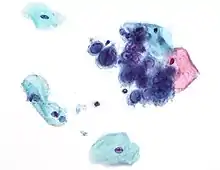

| TEM micrograph of virions of a herpes simplex virus species | |